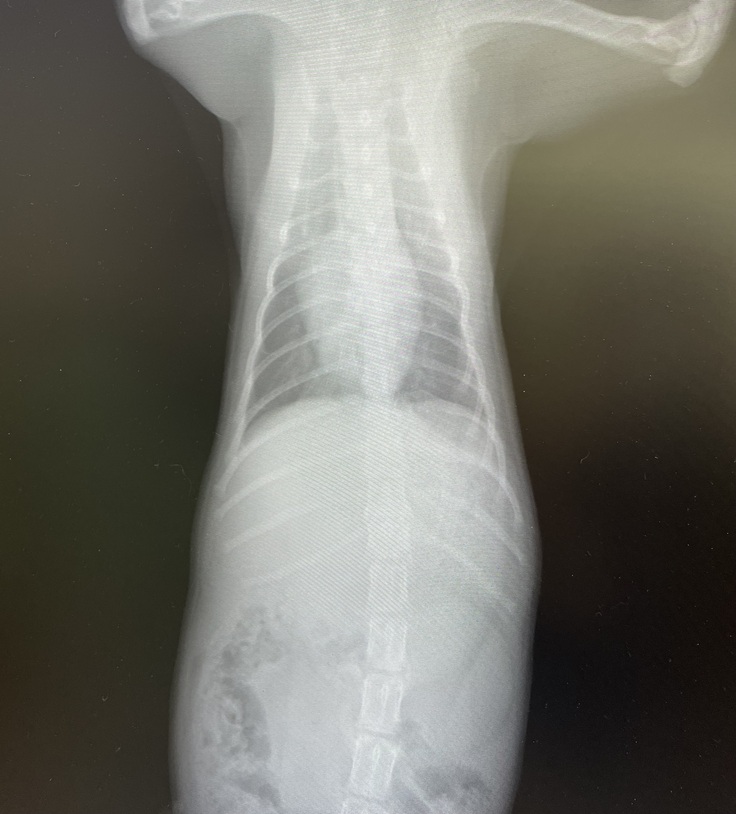

まずはレントゲンを撮ってもらいました。

エルちゃんのお腹の中、以前と比べるととっても綺麗になっていました😭

先生も、「もう問題ないし、大丈夫だね!エルちゃん本当に本当によく頑張ったね。お母さんが大事にお世話してくれたおかげだね。」と言ってくださいました。